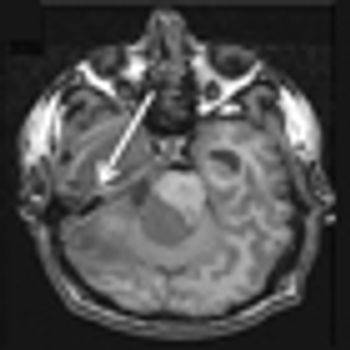

The patient is a 58-year-old woman who was diagnosed at an outside hospital with a World Health Organization (WHO) grade III non–contrast-enhancing right frontal anaplastic astrocytoma, with spread into the genu of the corpus callosum.